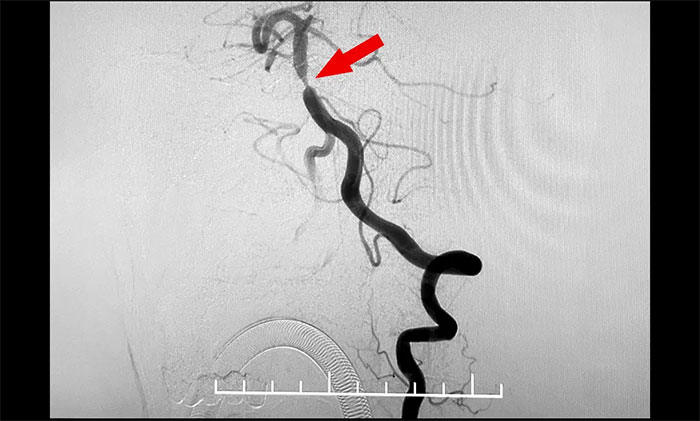

头颅MRI+SWI+DTI提示脑干梗塞,双侧桥臂变性;双侧放射冠区、额顶叶散在腔梗、缺血灶。基底动脉HRMR平扫+增强提示基底动脉管壁增厚伴重度狭窄。头颅CTP显示,右侧顶枕颞叶局部脑组织灌注较对侧稍减低。DSA提示基底动脉中段重度狭窄。

4A脑血管病一科主任席刚明教授,4A脑血管病一科副主任王贵平博士会诊指出,该患者为基底动脉主干病变,呈现为“一线天”样狭窄,考虑基底动脉重度狭窄为患者右侧肢体麻木并加重的根源。并且,狭窄处随时可能形成血栓引发血管急性闭塞,一旦闭塞,患者将可能出现深昏迷、四肢瘫痪,甚至危及生命,可以说“命悬一线”,即使侥幸保住性命,大概率也会成为植物状态或遗留其他严重残障。

▲ 基底动脉重度狭窄